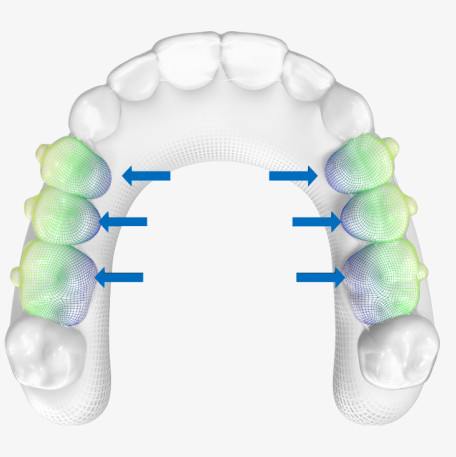

Posterior arch expansion solution with SmartForce optimized attachments & aligner activation

Reduction in the likelihood of posterior open bite (POB)

Invisalign G8 is designed to deliver more predictable posterior arch expansion.

SmartForce aligner activation is automatically programmed to apply and distribute the required force to each posterior tooth.

It is also designed to minimize unwanted molar tipping by automatically applying buccal root torque to the premolars and first molars.

Invisalign G8 reduces the likelihood of posterior open bite.

Provides more predictable anterior intrusion, which may reduce premature anterior contacts.

Controls unwanted buccal crown torque/tip during expansion.